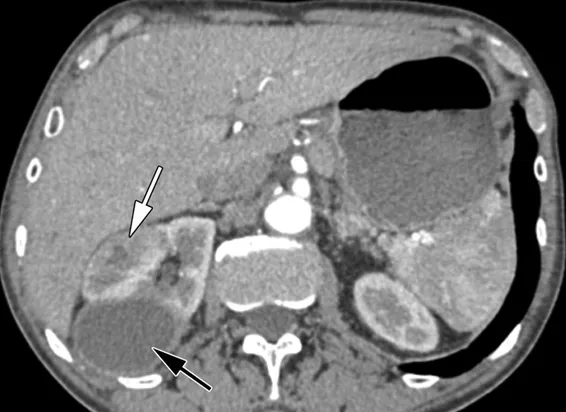

Você sabe quando suspeitar de infecção de cisto em pacientes com DRPAD? Nem toda febre é pielonefrite! Veja os achados clínicos e radiológicos que ajudam no diagnóstico, escolha os antibióticos com melhor penetração e evite falhas terapêuticas. Post indispensável para nefrologistas que lidam com infecção renal em pacientes com múltiplos cistos!

Valkercyo Feitosa